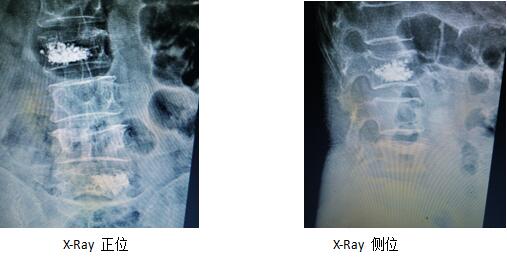

術(shù)前影像學(xué)片

術(shù)后復(fù)查片(骨水泥彌散均勻,無外漏)